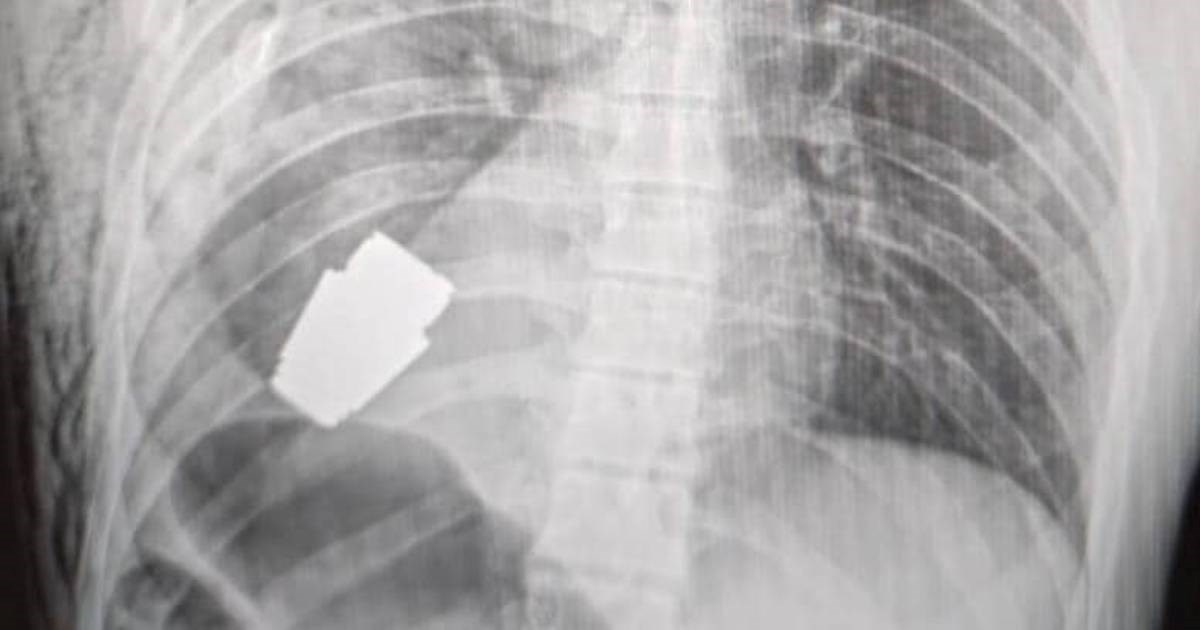

UKRAJINSKI vojni liječnik izvadio je dio nedetonirane granate iz tijela ranjenog vojnika, objavila je ukrajinska medicinska služba na Facebooku.